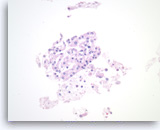

Benign pancreatic ductal cells,

Pancreas FNA, Direct Smear.

Normal pancreatic ductal cells are small and uniform, forming a cohesive monolayer sheet.

40X

Benign pancreatic ductal cells,

Pancreas FNA, Direct Smear.

Normal pancreatic ductal cells are small and uniform, forming a cohesive monolayer sheet.

40X